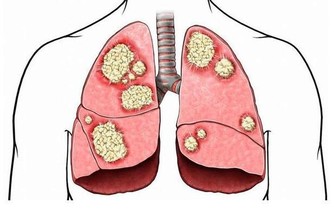

2、外界環境中的細菌易隨吸氣進入呼吸道及肺部。

(健康隱患:呼吸係統疾病)

遠離菸酒:在平日的生活中,煙、酒對於呼吸道的刺激,在AB型血的人中危害最大,所以要嚴格控製。

不宜吃過敏性食物:在所有血型中,AB型血的人患過敏性哮喘的比例最高,所以一切過敏性食物都要謹慎食用,比如魚、蝦、巧克力、羊肉等,以避免過敏性疾病的發生。